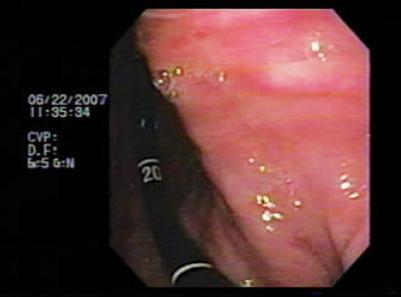

The patient was an 81 year old woman with arterial hypertension, and coronary disease in three arteries. She was bedridden due to a stroke which had occurred six months earlier. The patient was sent to our hospital for treatment of an intestinal obstruction. In the institution she had an upper digestive tract x-ray (Figure 1). When interviewed the patient described a 4 month long episode that had intensified in the previous 8 days. It was characterized by abdominal pain, vomiting, abdominal distension and melena. A physical examination showed generally poor physical condition, with dehydration, pain upon abdominal palpation, and left hemiparesis. The patient was referred for digestive endoscopy which found an organoaxial gastric volvulus and a hiatal hernia (Figure 2). Given the poor condition of the patient, and the absence of ischemia and gastric necrosis, it was decided to perform an endoscopic devolvulation using the technique described in 1995 by Tsang and colleagues (Figure 3).This technique has 6 steps. The initial aim is to create an alpha shaped loop (Figure 4) in the proximal end of the volvulated stomach. Next, the tip of the endoscope is advanced through the location of the stenosis produced by the volvulus. The following three steps aim to take the end of the endoscope to the duodenum (Figure 5). Once there, clockwise torque is endoscopically applied to complete the devolvulation (Figure 6). Since the patient was in poor condition, we decided to create two gastrostomies in the gastric wall: a distal gastrostomy for feeding, and one in the proximal body that was then sealed (Figure 7). The subsequent evolution of the patient was satisfactory.

Figure 1. The contrast x-ray shows an organ-axial volvulus, note the stenosis in the middle of the picture and the two bubbles formed due to the rotation.